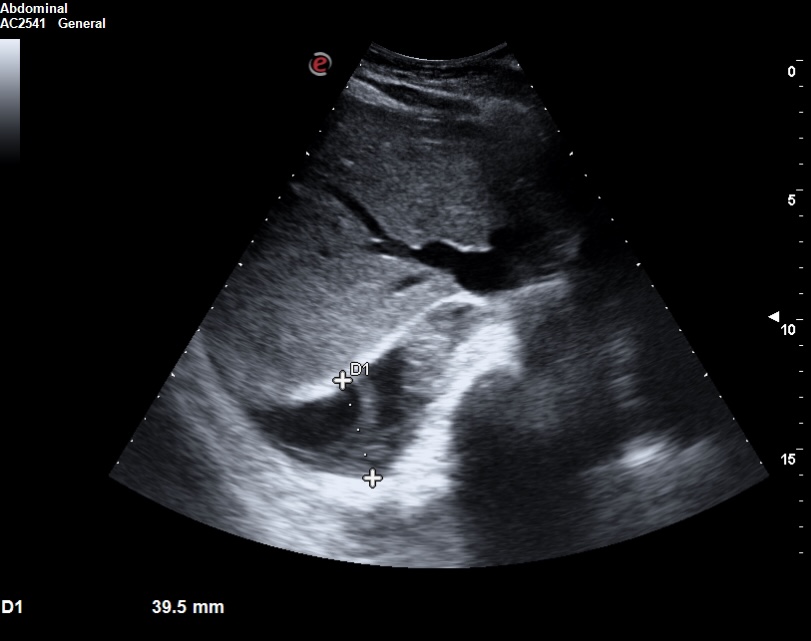

La ecocardioscopia mostró ventrículo izquierdo no dilatado con función sistólica conservada, sin hipertrofia del septo interventricular ni valvulopatías. Aurículas izquierda y cavidades derechas de tamaño normal. TAPSE normal. Se evidenció un derrame pericárdico moderado sin signos de taponamiento cardíaco. Calibre de vena cava inferior normal con colapsabilidad mayor del 50%. Hallazgo de derrame pleural derecho moderado.

La ecografía clínica desempeñó un papel fundamental en la evaluación inicial del paciente, permitiendo una detección rápida y precisa de hallazgos que guiaron la toma de decisiones clínicas. La ecocardioscopia realizada reveló un derrame pericárdico moderado, sin signos de taponamiento cardíaco y un derrame pleural derecho significativo. Estos hallazgos fueron esenciales para descartar la presencia de un cuadro obstructivo que pudiera haber requerido una intervención inmediata. Además, la ecografía permitió valorar el estado hemodinámico de la paciente de forma no invasiva, asegurando que el derrame pericárdico no comprometiera la función cardíaca. En la radiografía de tórax se objetiva una masa mediastínica. La capacidad de detectar y cuantificar de forma precisa tanto el derrame pleural como el pericárdico sin necesidad de esperar a pruebas más complejas, permitió que la paciente fuera ingresada de manera adecuada para un estudio exhaustivo y sin demoras innecesarias.